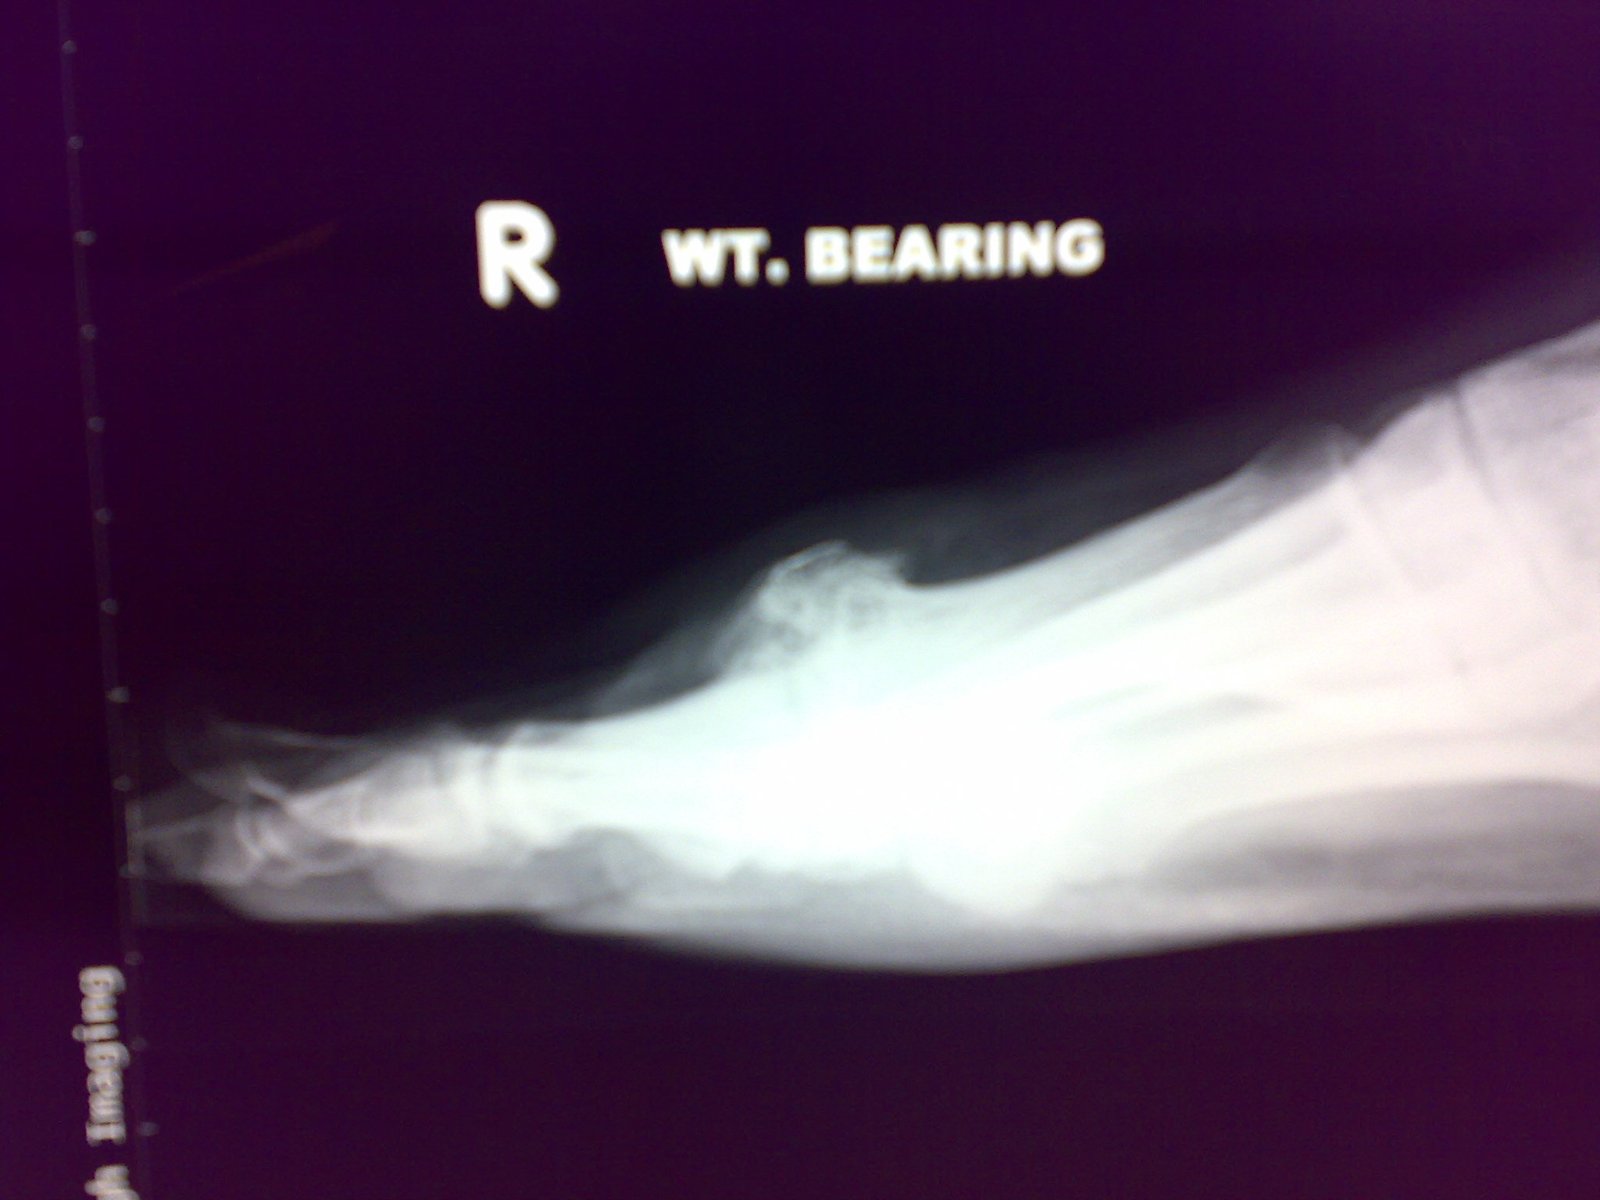

How do we diagnose arthritis in the big toe joint?

This is done with a simple X-ray. The X-ray will be assessed, and the spurring, loss of joint space and various other signs are apparent to see. During a consultation, the joint will be evaluated for range of motion, and the presence of spurring will be checked. The joint will often creak or grind as it is moved.